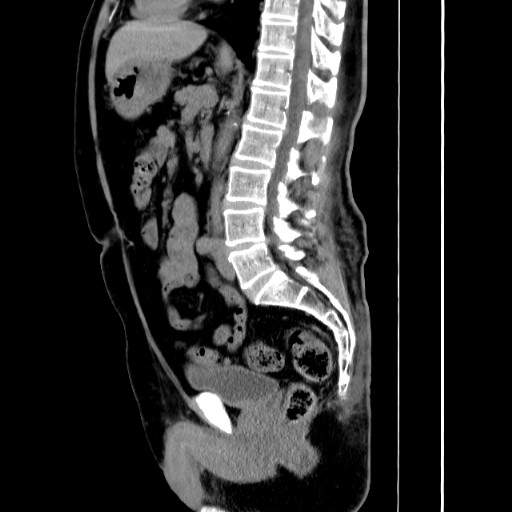

肛門周辺の病変を詳しく調べることができます。肛門周囲膿瘍の広がりや痔瘻の走行、直腸癌や進行大腸癌、前立腺や子宮.卵巣の病気なども検出可能です。

直腸肛門疾患に特化したCT撮影法

当院では、肛門・直腸疾患に特化した独自のCT撮影法を行っています。

従来の腹部CTが仰向けで撮影するのに対し、この方法ではうつぶせで撮影し、さらに直腸の形や走行に合わせて断面角度を調整することで、肛門周囲の病変をより鮮明に映し出すことが可能です。

また、3D画像によって痔瘻の走行を立体的に描出することもできます。

一般的撮影法

肛門病変に特化した撮影法